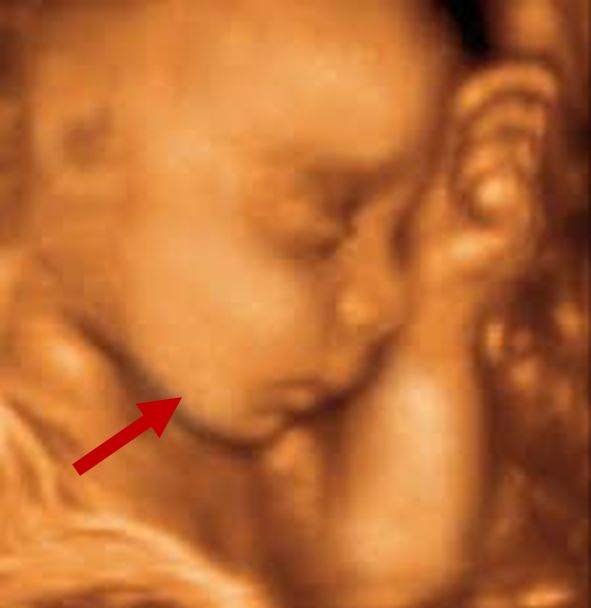

Mandibular hypoplasia

Prenatal 3D\4D ultrasound showing underdeveloped mandible

Radiographical features source 2